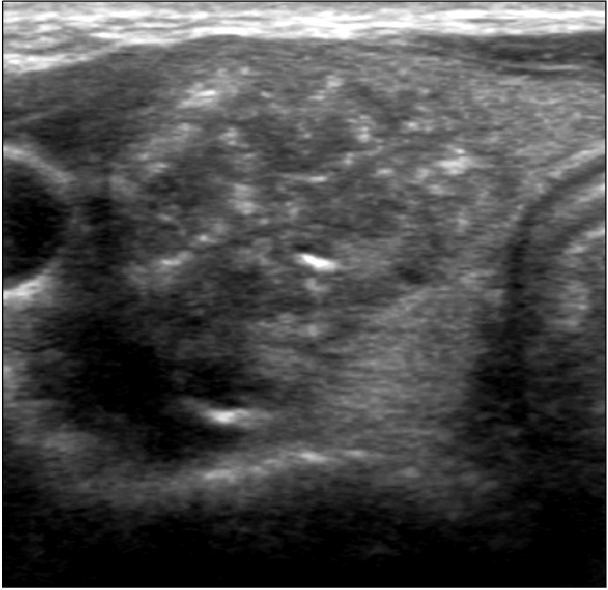

- Siêu âm tuyến giáp, đánh giá các đặc điểm hình ảnh để phân loại nguy cơ ác tính (TIRADS) và chọc hút tế bào u giáp dưới hướng dẫn siêu âm nếu nghi ngờ ung thư.

Hình ảnh siêu âm tuyến giáp. U thùy trái tuyến giáp có canxi hóa vi thể, phân độ TIRADS 5